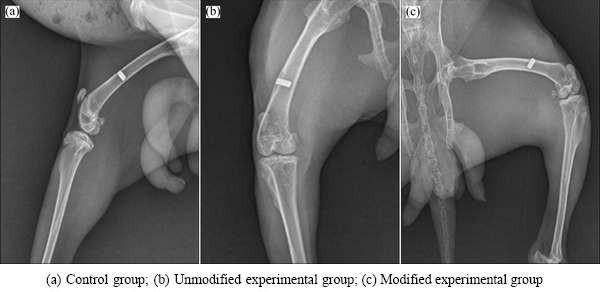

X-ray examinations after postoperative 4 weeks revealed no sign of bone dissolution or X-ray translucent areas in the implants of the two experimental groups and the control group. No obvious gap, but rather close integration, was found between the implants and adjacent bones. However, no significant signs of osteogenesis were found at the early stage of bone healing. X-rays taken after postoperative 8 weeks showed no significant changes in the dense titanium control group compared to 4 weeks; however, the integration between the modified and unmodified porous titanium and the implant-adjacent tissues was closer with new bone formation at 8 weeks compared to 4 weeks. Results after 12 weeks (Fig. 5) showed no loosening or bone resorption between these three groups of implant materials and their adjacent bone tissues. Bone density adjacent to implants of the modified and unmodified experimental groups was increased, but no significant increase of new bone mass was found.

Fig. 5 X-ray images of different implant specimens after postoperative 12 weeks